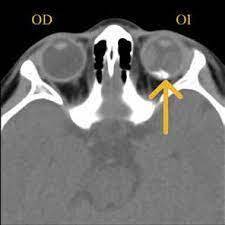

¿Cuáles son los hallazgos radiológicos en la TC de la obitopatía tiroidea?

La TC en orbitopatía tiroidea se usa para ___, mientras que la RM se usa para __.